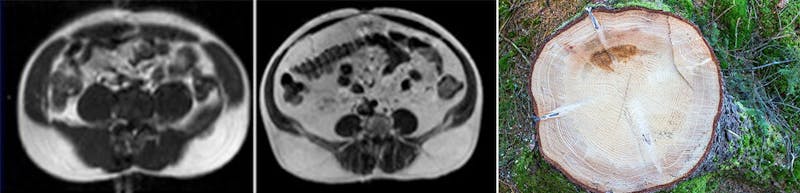

Aquí puedes ver dos escaneos de dos pacientes con la misma circunferencia de cintura. Para entender lo que estás viendo, imagina mirar todos los círculos dentro de un árbol cortado.

A la izquierda puedes ver que hay bastantes músculos. Son los círculos oscuros que ves justo debajo de la capa blanca exterior de grasa.

A la derecha, puedes ver una capa muy delgada de músculos debajo de la grasa. También puedes ver MUCHA grasa blanca dentro de la cavidad abdominal. Hay grasa por todo lados, alrededor y dentro de los órganos. A estas personas las denominamos DFGD, que significa delgado por fuera, gordo por dentro. Una persona DFGD puede verse normal o saludable, pero las apariencias pueden engañar.